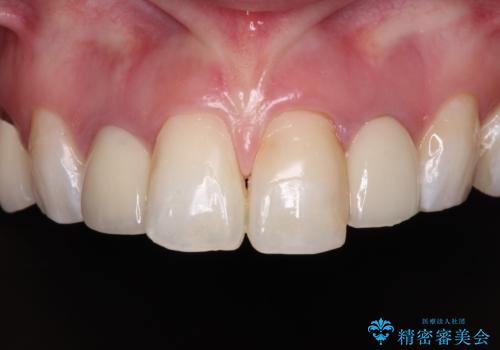

金属の見えてしまったクラウン セラミッククラウンで自然に